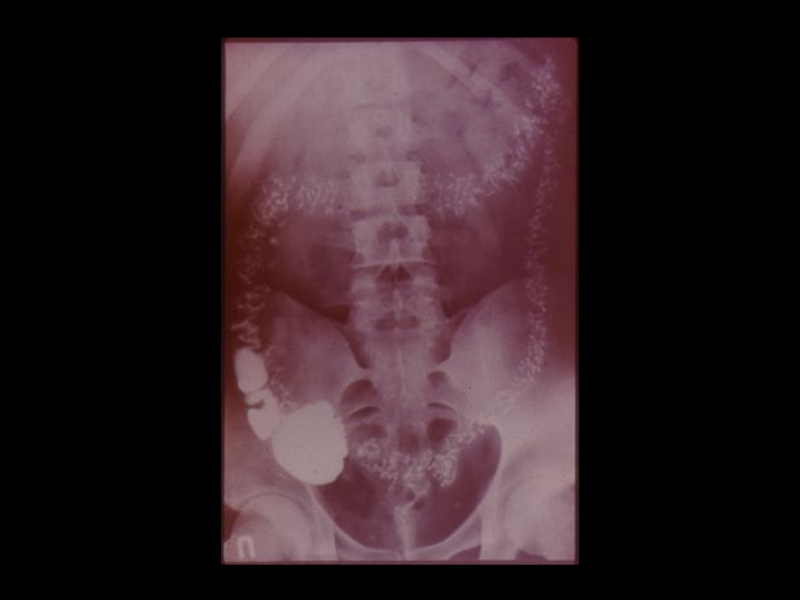

Слайд 37Задачи искусственного контрастирования органов:

1. Получение изображения органов , не обладающих

естественной контрастностью

2. Повышение разрешающей способности методов, за

счет повышения качества изображения и создания

эффекта «усиления»

3. Осуществление контроля при проведении

интервенционных мероприятий, проводимых с

помощью лучевых методик.

Задачи искусственного контрастирования органов:1. Получение изображения органов , не обладающих   естественной контрастностью2. Повышение разрешающей способности